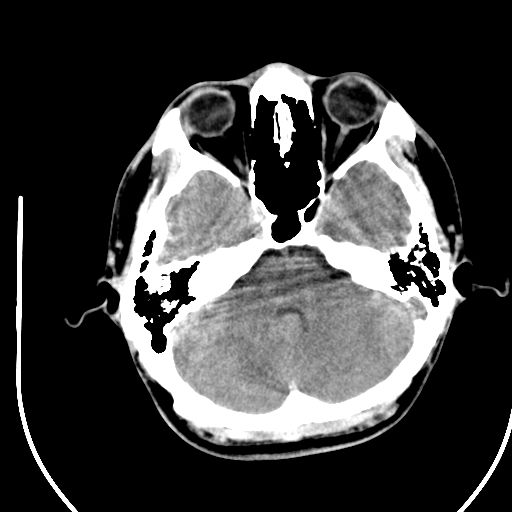

标题: CT28158:男,27Y。头痛数月,左顶叶血管瘤。 [打印本页]

标题: CT28158:男,27Y。头痛数月,左顶叶血管瘤。

考虑avm。

考虑avm。  建议dsa检查。

海绵状血管瘤

考虑左顶叶海绵状血管瘤,建议mr检查。

左侧额叶海绵状血管瘤可能性大;建议行mri检查。

考虑血管畸形,因其周可见水肿,不除外感染性病灶。建议mri检查。